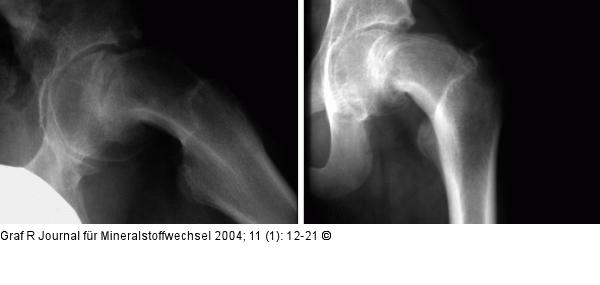

Abbildung 9: Hüftgelenk Epiphyseolysis capitis femoris, Röntgen ap und axial. Das Abrutschen des Hüftkopfes am Schenkelhals ist deutlich sichtbar. |

Epiphyseolysis capitis femoris, Röntgen ap und axial. Das Abrutschen des Hüftkopfes am Schenkelhals ist deutlich sichtbar. |